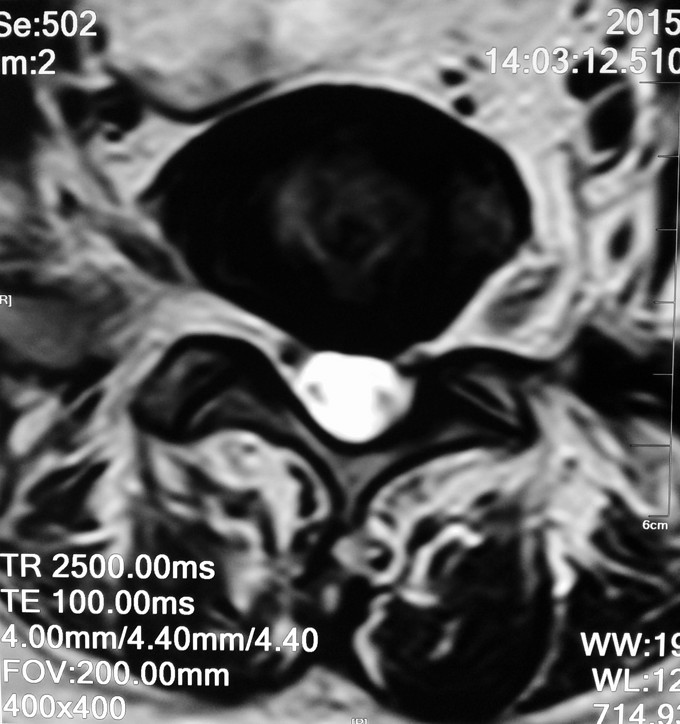

患者女性,58岁。 腰痛间断性发作2年,加重伴左下肢疼痛不适4月 疼痛以久坐和劳累后症状明显,近4月上述症状加重,伴有左下肢麻木疼痛感,经卧床休息后不能缓解。

腰3-4/4-5间隙及椎板压痛及叩击痛,无明显下肢放射痛。左大腿前外侧及膝以下感觉有减退,左侧髋、膝肌力5级,拇趾背伸肌力4级,肌张力不高,左下肢直腿抬高试验40°阳性,加强试验阳性。右下肢感觉肌力正常。 血沉 99mm/h C反应蛋白:4.1ng/L 斑点试验:抗A 111,kangB 127

1.腰3-4结核 2.腰4-5椎管狭窄 因术前血沉比较高,所以予以HREZS抗痨治疗2周,血沉至44mm/h,患者一般情况较前好转。安排手术治疗:后路腰3-4椎间病灶清除椎板植骨+腰4-5减压植骨内固定融合术。

此患者腰椎结核伴有相邻节段椎管狭窄,所以兼有两者的症状。对于此病例我们考虑因患者椎体前方脓肿不明显,所以考虑一起行后方椎间隙病灶清除,植入自体椎板骨融合内固定,同时进行腰4-5后路减压内固定融合术。 不知大家对结核的病人一般是通过何种方式进行病灶清除的?选择原则是什么?